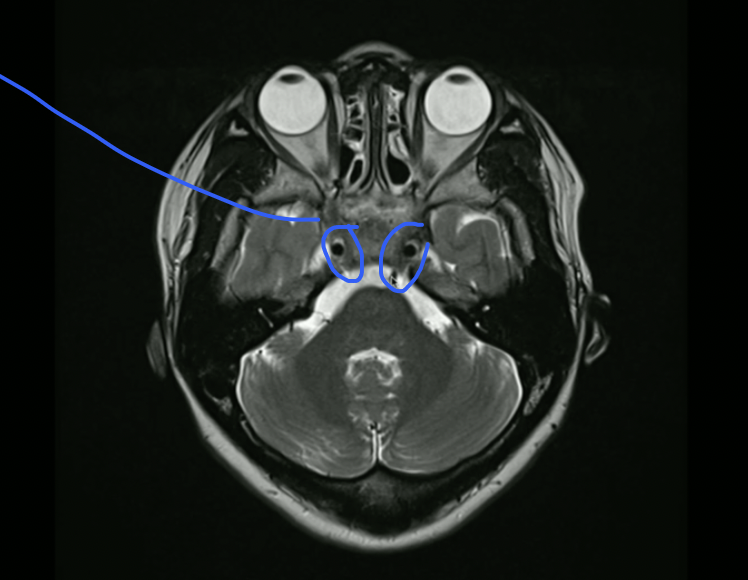

<p>What nerve travels here?</p>

What nerve travels here?

• CN 3 (3 and 4 are at level of midbrain)